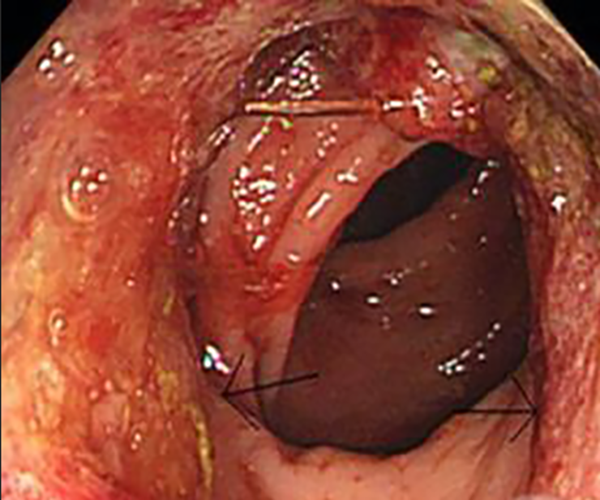

炎性胃息肉切除

胃息肉做手術

胃息肉治療前後

A:胃鏡息肉切除一般需要休息3-5天,胃鏡息肉切除是指通過胃鏡,將胃內的息肉樣病變進行電切,切除之後局部會留有潰瘍面,必要時可以用金屬夾封閉創面,切除之後要觀察創面是否會出現出血,或者穿孔等併發症,所以手術之後一般要在醫院觀察1-2天,以便及時……